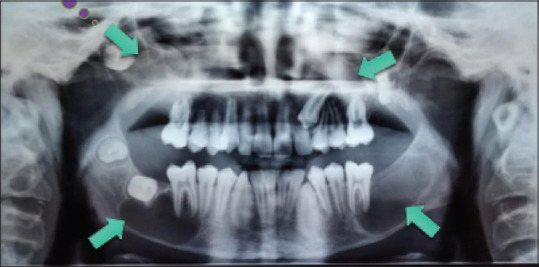

Diagnosis: Orthopantomogram was taken and it showed multiple radiolucent areas present in the maxilla and mandible. Aspiration of the cystic lesion was done under local anaesthesia and it yielded a cheesy exudate which is characteristic of OKC.